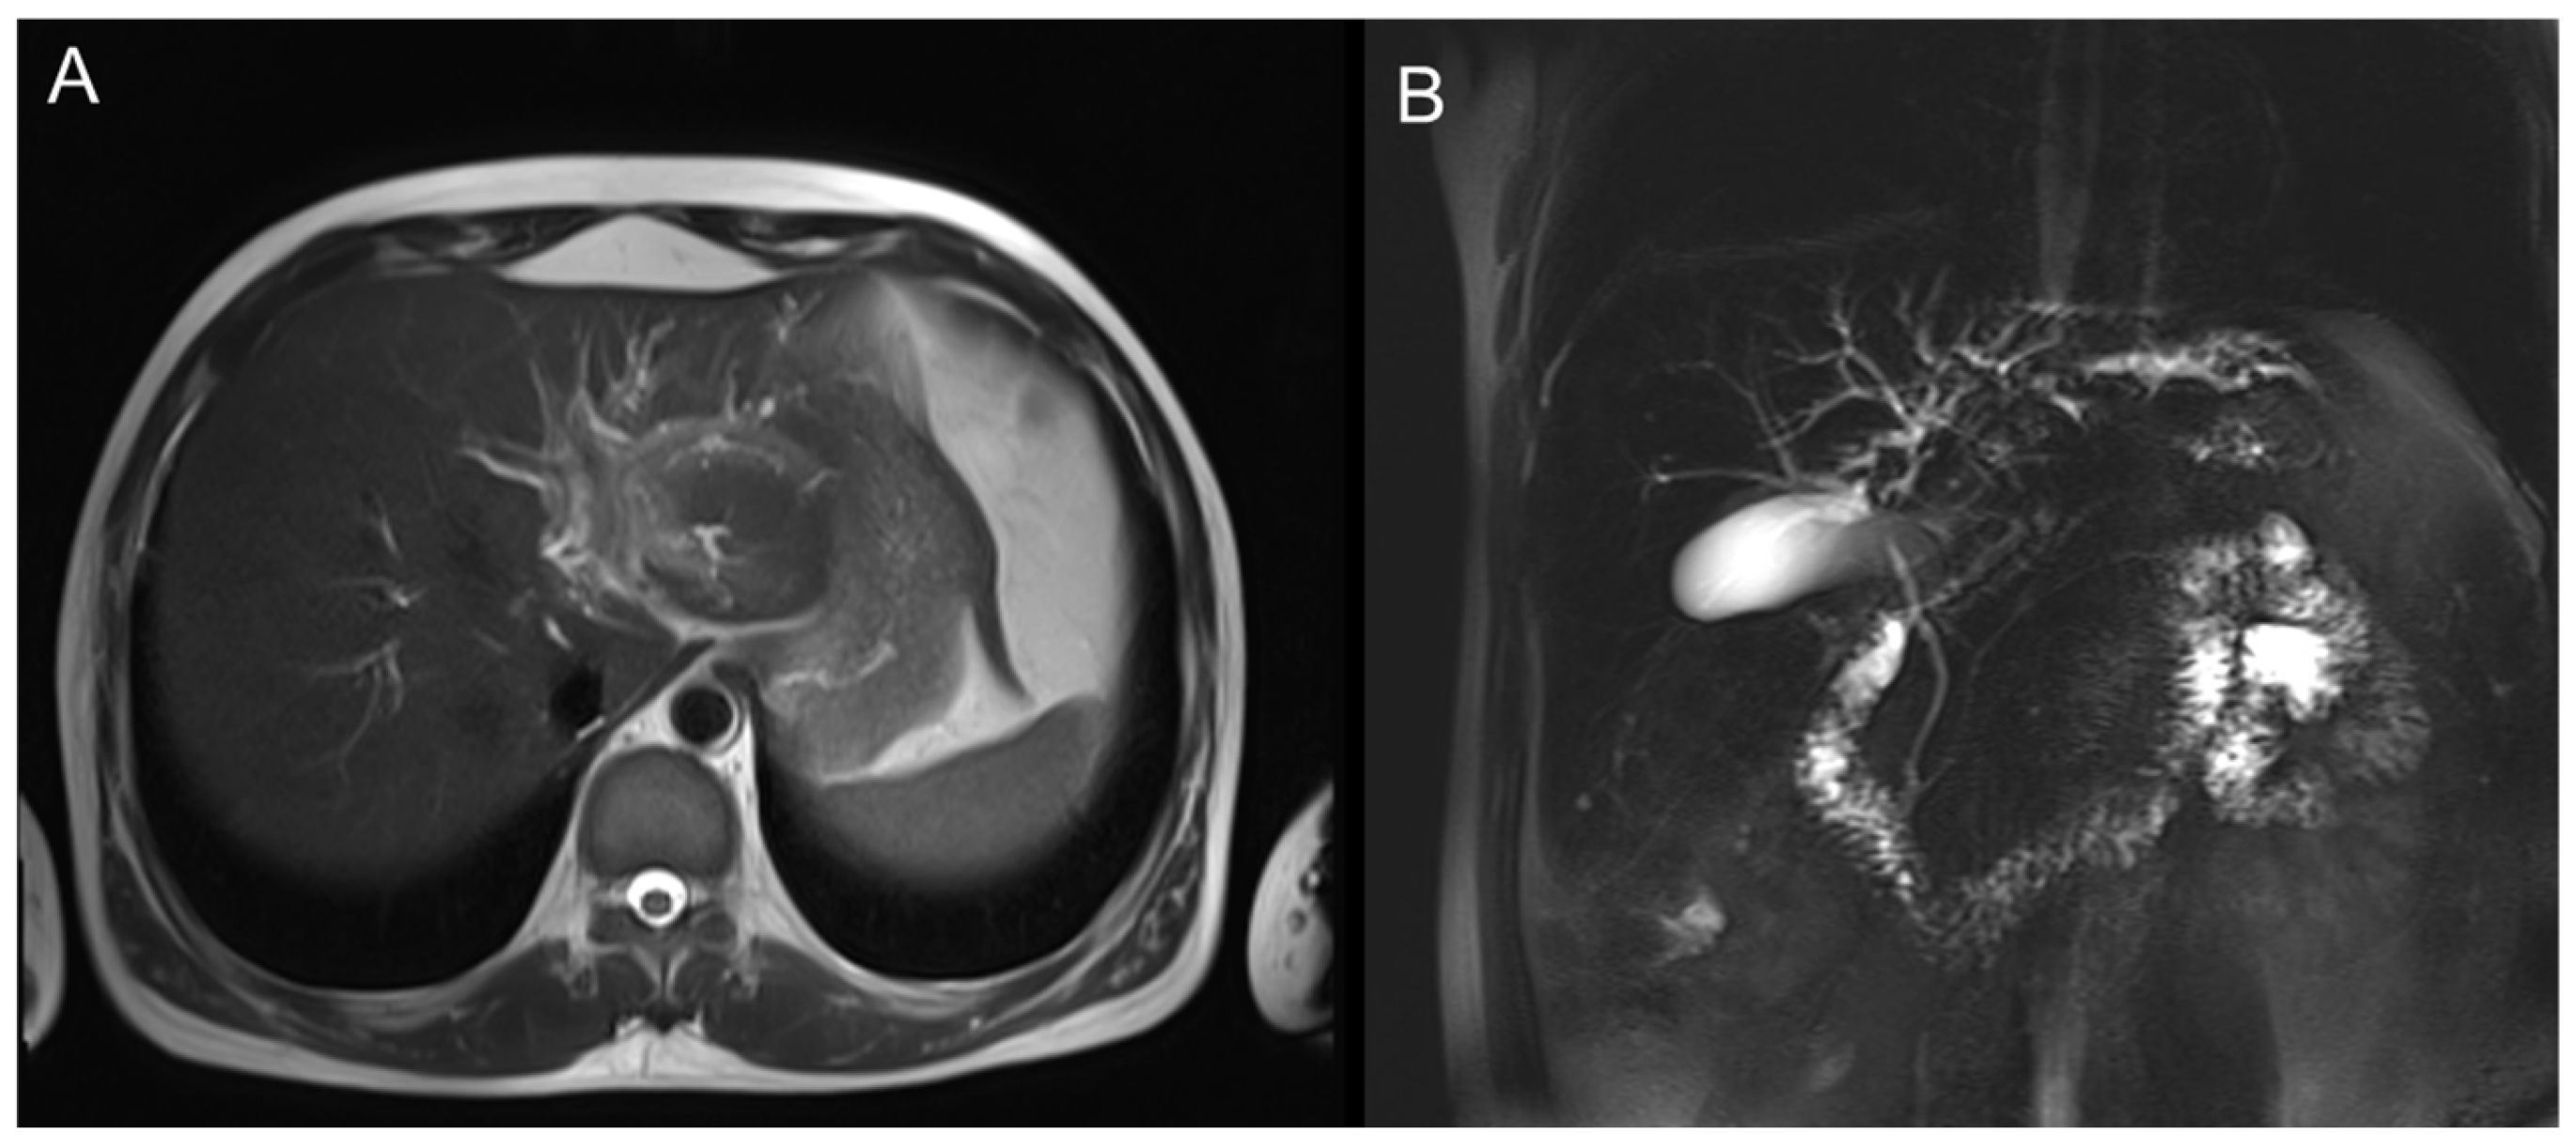

CT revealed patchy low-density lesions in the left hepatic lobe and hilar region, with mild intrahepatic bile duct dilatation and local bile duct wall thickening. The largest lesion was about 14 mm in diameter. Multiple enlarged lymph nodes were seen in the hepatic hilum and hepatoduodenal ligament areas. Malignancy, such as cholangiocarcinoma, was suspected (Figure 1).

Figure 1. Axial contrast-enhanced CT images of the liver. (A) Plain scan shows a patchy low-density lesion in the left lobe of the liver near the hepatic hilum. (B) Arterial phase shows mild heterogeneous enhancement of the lesion.